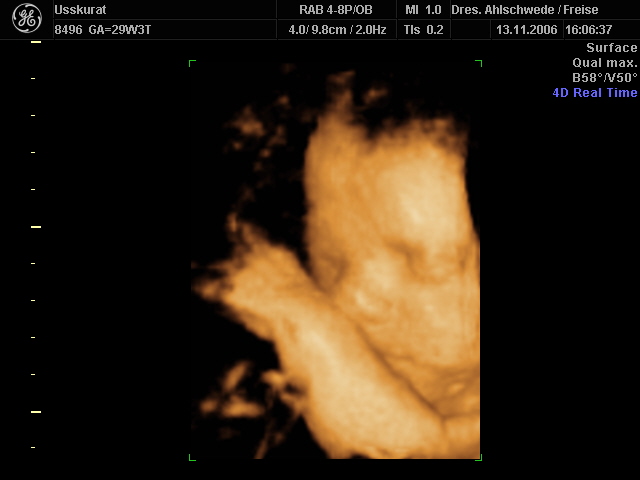

Wow,Claerchen,ist das ein schööönes Bild!

Ich bin ja immer wieder begeistert,wie deutlich das Alles heutzutage ist!

Sowas gab's zu meiner Zeit ja nicht..schluchz

Claerchen, davon hab ich auch schon gehört,dass Babys von Diabetiker schon größer werden können..

Aber es könnte doch auch genau sogut sein,dass Lieselottchen einfach nur ein großes Kind ist..schließlich liegt sie ja in der Norm!

...Sie ist einfach ein strammes Mädel!!

Und das Bild fasziniert mich echt total...zu süüüüüüßßßß..will auch haben..